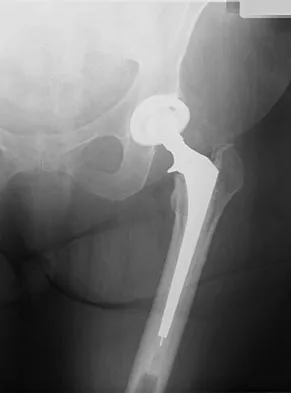

Question 31 High Yield

Figure 17 shows the radiograph of an 80-year-old woman who has left groin pain. She underwent a total hip arthroplasty 15 years ago and has no history of hip dislocation; however, she now reports that the pain results in functional impairment. Preoperative findings reveal that the component used has been discontinued, the locking mechanism is poor, and there is no replacement polyethylene available from the company. During surgery, the acetabular component is found to be well fixed, it is in satisfactory position, and adequate access can be obtained through the screw holes in the component to debride the osteolytic cavities. What is the best course of action for revision?

Detailed Explanation